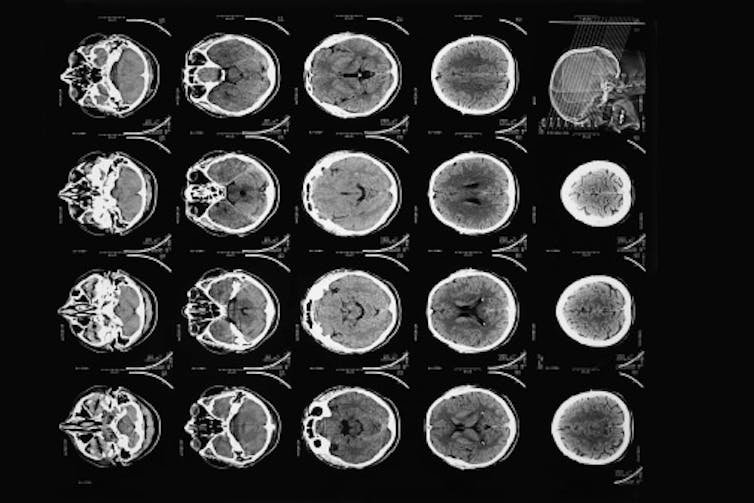

The first computed tomography image – a CT scan – of the human brain was made 50 years ago, on Oct. 1, 1971. Hounsfield never made it to Egypt, but his invention did take him to Stockholm and Buckingham Palace.

First, he would conceptually divide the brain into consecutive slices – like a loaf of bread. Then he planned to beam a series of X-rays through each layer, repeating this for each degree of a half-circle. The strength of each beam would be captured on the opposite side of the brain – with stronger beams indicating they’d traveled through less dense material.

Finally, in possibly his most ingenious invention, Hounsfield created an algorithm to reconstruct an image of the brain based on all these layers. By working backward and using one of the era’s fastest new computers, he could calculate the value for each little box of each brain layer. Eureka!

It was not a fast process – 30 minutes for the scan, a drive across town with the magnetic tapes, 2.5 hours processing the data on an EMI mainframe computer and capturing the image with a Polaroid camera before racing back to the hospital.

And there it was – in her left frontal lobe – a cystic mass about the size of a plum. With that, every other method of imaging the brain was obsolete.